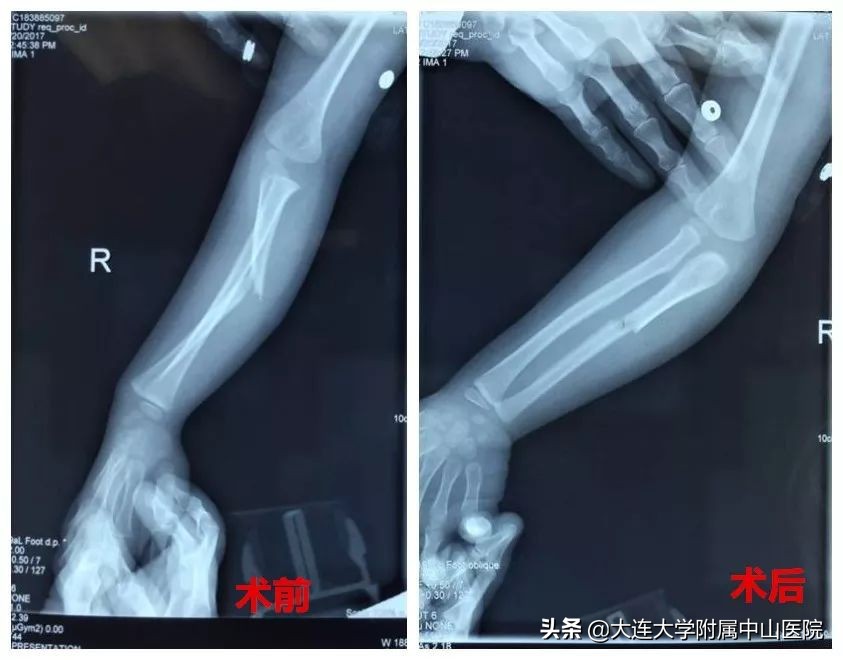

夏重君主任介绍,在骨科中,造船分部骨科具有鲜明的技术特色,有最具特色的传统手法复位技术,各个病区的骨科医生都能熟练掌握这个技术,让无数骨折患者免去了手术的困扰。还有特制小夹板固定技术……这些特色技术实现了骨折的无创治疗;对于需要手术的骨折患者,采用手法复位结合闭合复位等微创技术,让患者少遭罪,也减少了经济负担。针对儿童手法复位中的疼痛和不配合等情况,科室在2017年在全国首创床旁镇痛手法复位,让接受手法复位的儿童患者更加舒适安全的接受复位治疗。

案例回放